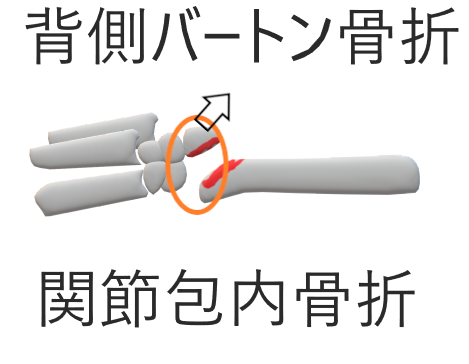

4.辺縁部骨折(掌側バートン、背側バートン)

(発生)

コーレス、スミス骨折と同様に手をついて転倒

※橈骨関節面に骨折線が及ぶ⇒関節内骨折

安定性悪く観血療法の適応になることが多い

背側バートン

(症状)

遠位骨片は手根部と共に背側転位。橈骨手根関節は不全脱臼

(整復法)

回外位に末梢牽引を行い、手関節の伸展とともに背側から掌側へ遠位骨片を圧迫して整復

(固定)

範囲:肘関節を含みMP手前まで

肢位:手関節軽度伸展、回外位、肘90°